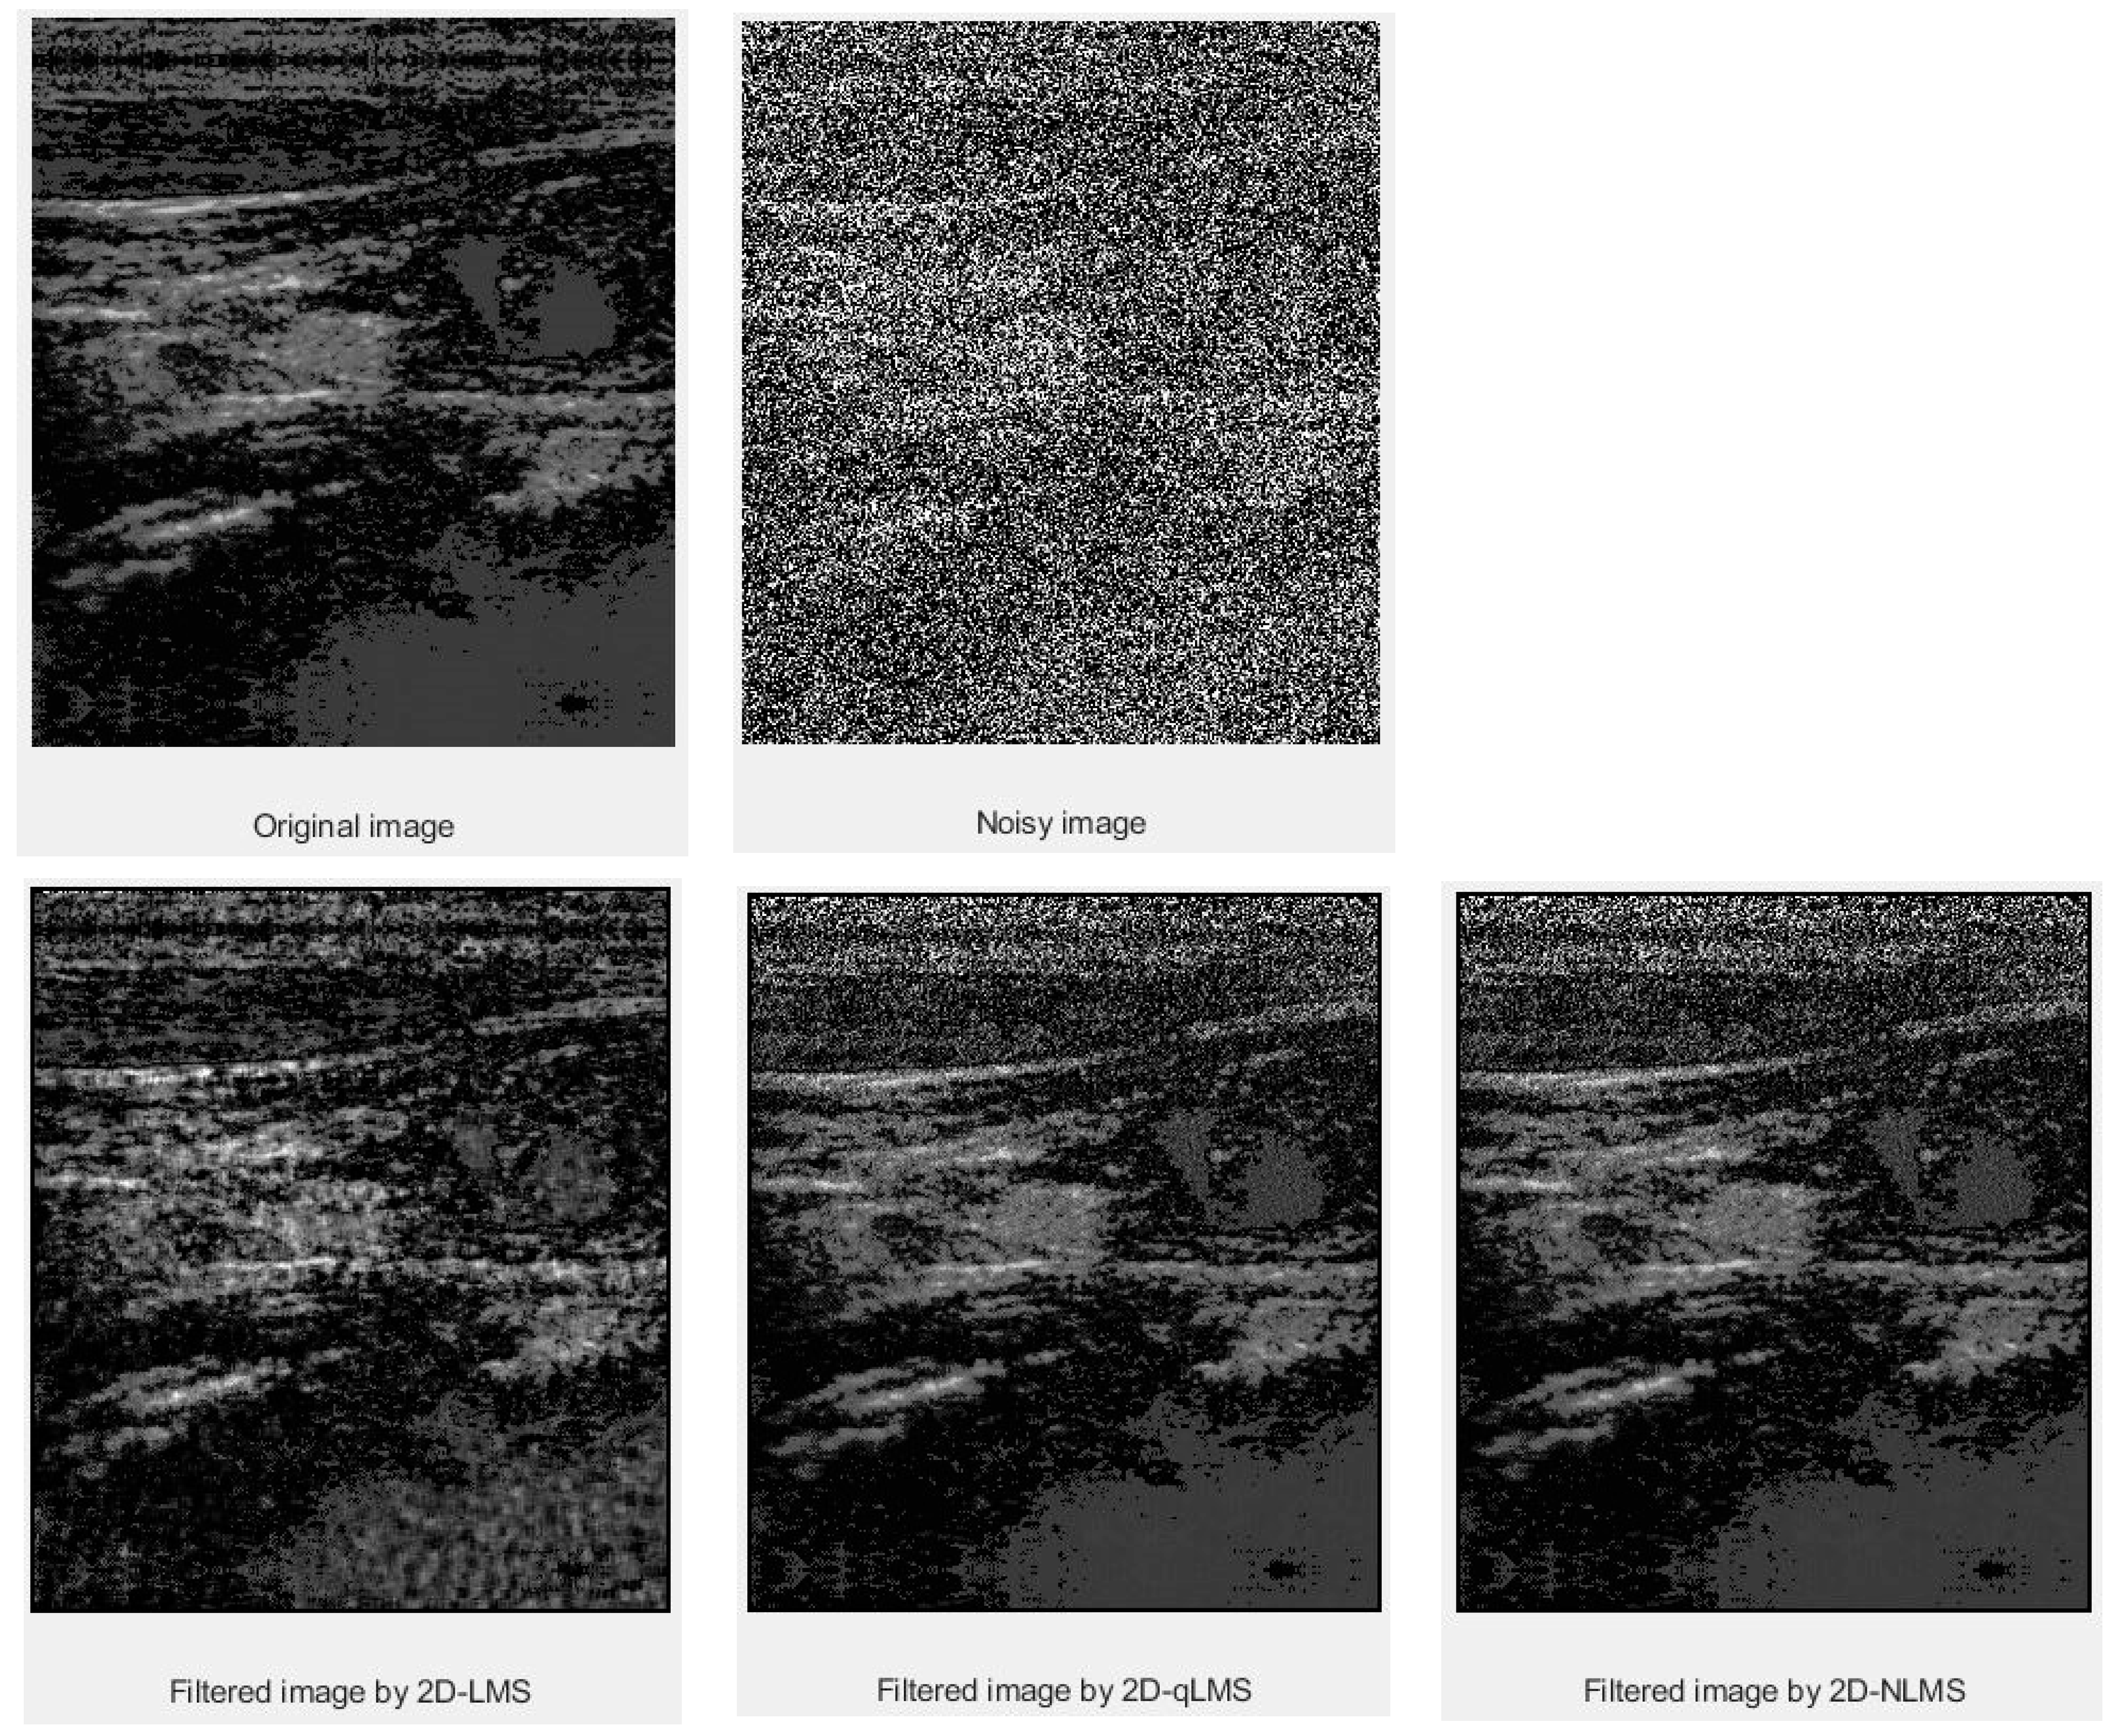

3. Results and Discussion

3.1. PSNR Values

3.2. SSIM Values

| Data | Filter Size | LMS | QLMS | NLMS |

|---|---|---|---|---|

| Thyroid | 5 × 5 | 64.0167 | 70.0593 | 72.8341 |

| Thyroid Cyst | 5 × 5 | 64.0506 | 69.1289 | 72.8708 |

| Mass in Muscle | 5 × 5 | 63.8117 | 69.1211 | 72.2958 |

| Data | Filter Size | LMS | QLMS | NLMS |

|---|---|---|---|---|

| Thyroid | 5 × 5 | 0.9996 | 0.9997 | 0.9998 |

| Thyroid Cyst | 5 × 5 | 0.9993 | 0.9997 | 0.9999 |

| Mass in Muscle | 5 × 5 | 0.9996 | 0.9998 | 0.9999 |